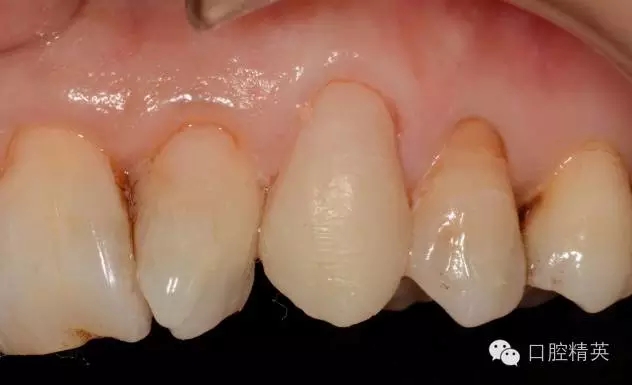

圖10 修復(fù)體代入口內(nèi)照

圖12 修復(fù)體代入口內(nèi)正面照